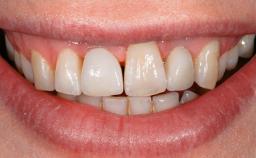

A 77-year-old male patient was referred for the management of frequent and repeated acrylic fracture of his existing mandibular fixed full-arch implant-supported metal/acrylic prosthesis. He also complained about softtissue soreness and the lack of retention and stability of his maxillary removable partial metal/acrylic prosthesis. Both prostheses had been delivered two years previously as part of his full-mouth rehabilitation (caries, tooth wear, tooth fracture). His medical history revealed high blood pressure, controlled with the use of antihypertensive medication.

Patient's Esthetic Expectations | Low | Medium | High |

Lip Line | No exposure of papillae | Exposure of papillae | Full exposure of mucosa margin |

Shape of Tooth Crowns | Rectangular | Triangular | |